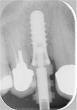

Implantáció

Az implantátumok biológiailag semleges titánból készülnek, felszínük speciális eljárás során kiváló rögzülést biztosít a csontos környezethez. A foghiányok helyére, az állkapocsban kerülnek elhelyezésre (implantálásra). A beültetést követően kb. 12 hét gyógyulási időre van szükség, mialatt a csont benövi az implantátumot, és így az biztosan rögzül a csontban. A gyógyulási időt követően kerül sor a felépítmény elkészítésére, melyet becsavarnak a mesterséges foggyökérbe, és minderre kerül a látható pótlás, a korona vagy hídtag.

A fogbeültetés egyik legfontosabb eleme annak megtervezése, az egész szervezet általános egészségi állapotának felmérése. A tervezésnek manapság elengedhetetlen feltétele a csontozat állapotának felmérése, a tervezett implantátum körüli csontállomány sűrűségének meghatározása Nem mindenkinek, és nem minden fogpótlásnál lehet, és kell implantálni. Az implantáció sikerességét, élettartamát nagymértékben befolyásolják általános betegségek, mint a cukorbetegség, a szív- és keringési rendszer megbetegedései, a csontbetegségek. Amennyiben semmi sem szól az implantálás ellen, úgy érzéstelenítés alatt kerülnek behelyezésre a mesterséges foggyökerek. Az, hogy kinek hány implantátumra van szüksége, azt egyénre szabottan a pótlandó foghiány nagyságától függően tudjuk meghatározni. Nagyobb foghiányok esetén nem szükséges minden fog helyére implantátum behelyezése, csupán a kívánt hosszúságú híd rögzítéséhez elegendő számú.

A Medconnexus Gyógyászati Központ az egyik legnevesebb piacvezető implantátumgyártó, a svájci "Straumann" cég termékeit alkalmazza. Hiszen ezen beavatkozások kapcsán semmiféle kompromisszumnak nincs helye.